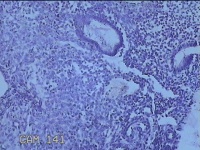

性别

女

年龄

46岁

临床诊断

子宫异常出血 子宫内膜炎? 息肉?

一般病史

阴道流血28天。

标本名称

子宫腔内膜

大体所见

纱布一块,内有灰白暗红色不规则碎组织1.5x1.3x0.3cm一堆。